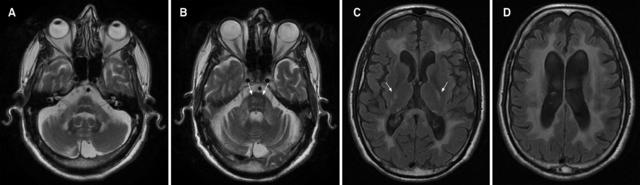

案例 1:36 岁男性,诊断为肾上腺脊髓神经病。

图 1 A~B:FLAIR 可见双侧深部白质,胼胝体体部和内囊高信号;C~D:T1 增强可见内囊和胼胝体体部病灶强化

案例 2:54 岁男性,诊断为肾上腺脑白质营养不良。

图 2 A~B:T2WI / FLAIR 提示双侧额叶皮质下、脑室旁和顶枕叶白质受累,同时可见内囊高信号。C:T1 增强提示额叶病灶周围轻度强化

案例 3:28 岁男性,诊断为肾上腺脑白质营养不良。数月前曾有右顶叶区外伤史。

图 3 A:FLAIR 证实右侧顶叶皮质下白质病灶;B:T1 增强可见病灶边缘非连续性强化;C:T2WI 可见异常信号延伸至内囊;D:DWI 可见病灶边缘高信号